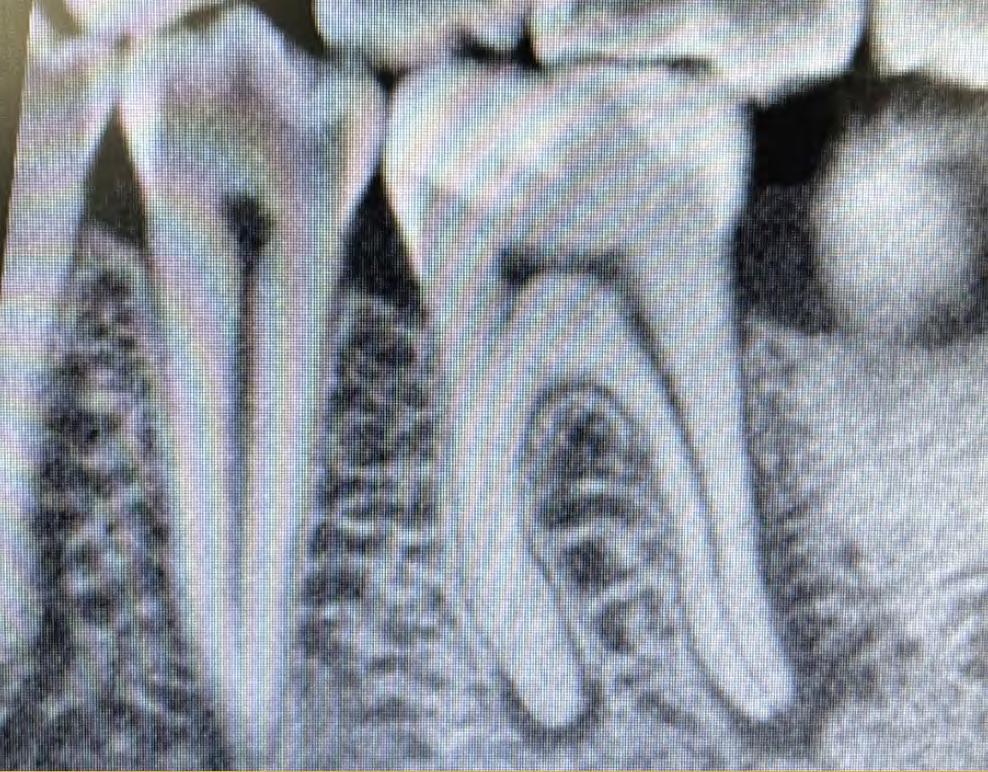

A 65 year old patient was referred for endodontic treatment of her second lower molar (#37). She reported a history of spontaneous pain, swelling and dental fistula. Proceeding pulp vitality tests and radiographic examination, the tooth was diagnosed with symptomatic apical periodontitis.

Looking at this pre-operatory radiograph, two information regarding this endodontic case should be detected (Fig.1):

Obliterated pulp chamber and narrow canals

The non-conventional anatomy of distal root

Case Report Fig.1